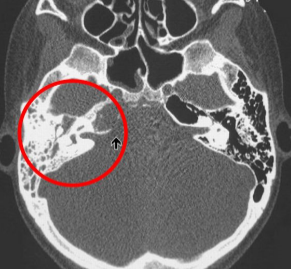

estudio de imagen para mastoiditis

TC

- opacificacion de celdillas mastoideas

- cronico: esclerodiploico (engrosamiento óseo)